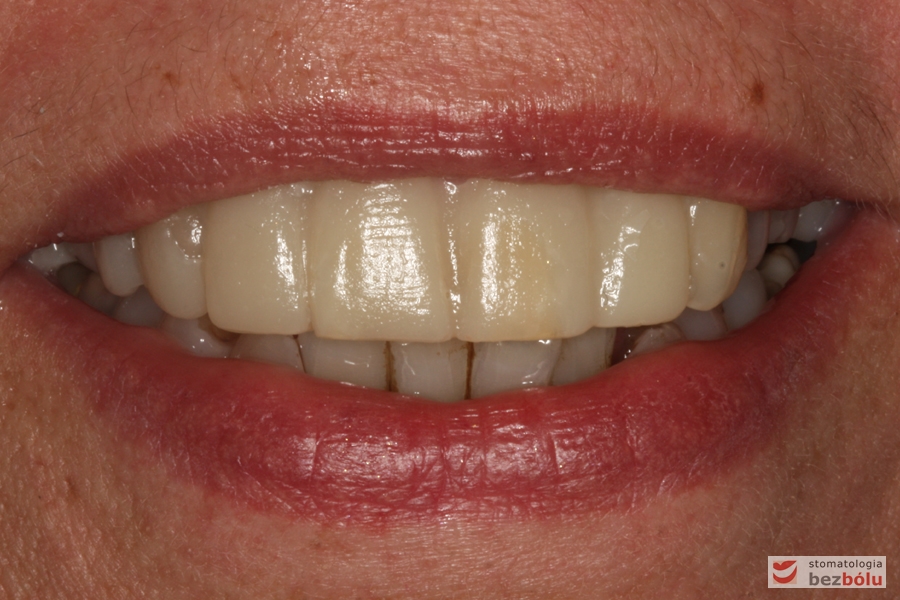

Efekt końcowy leczenia - nowe zęby w uśmiechu

Efekt końcowy leczenia – nowe zęby w uśmiechu